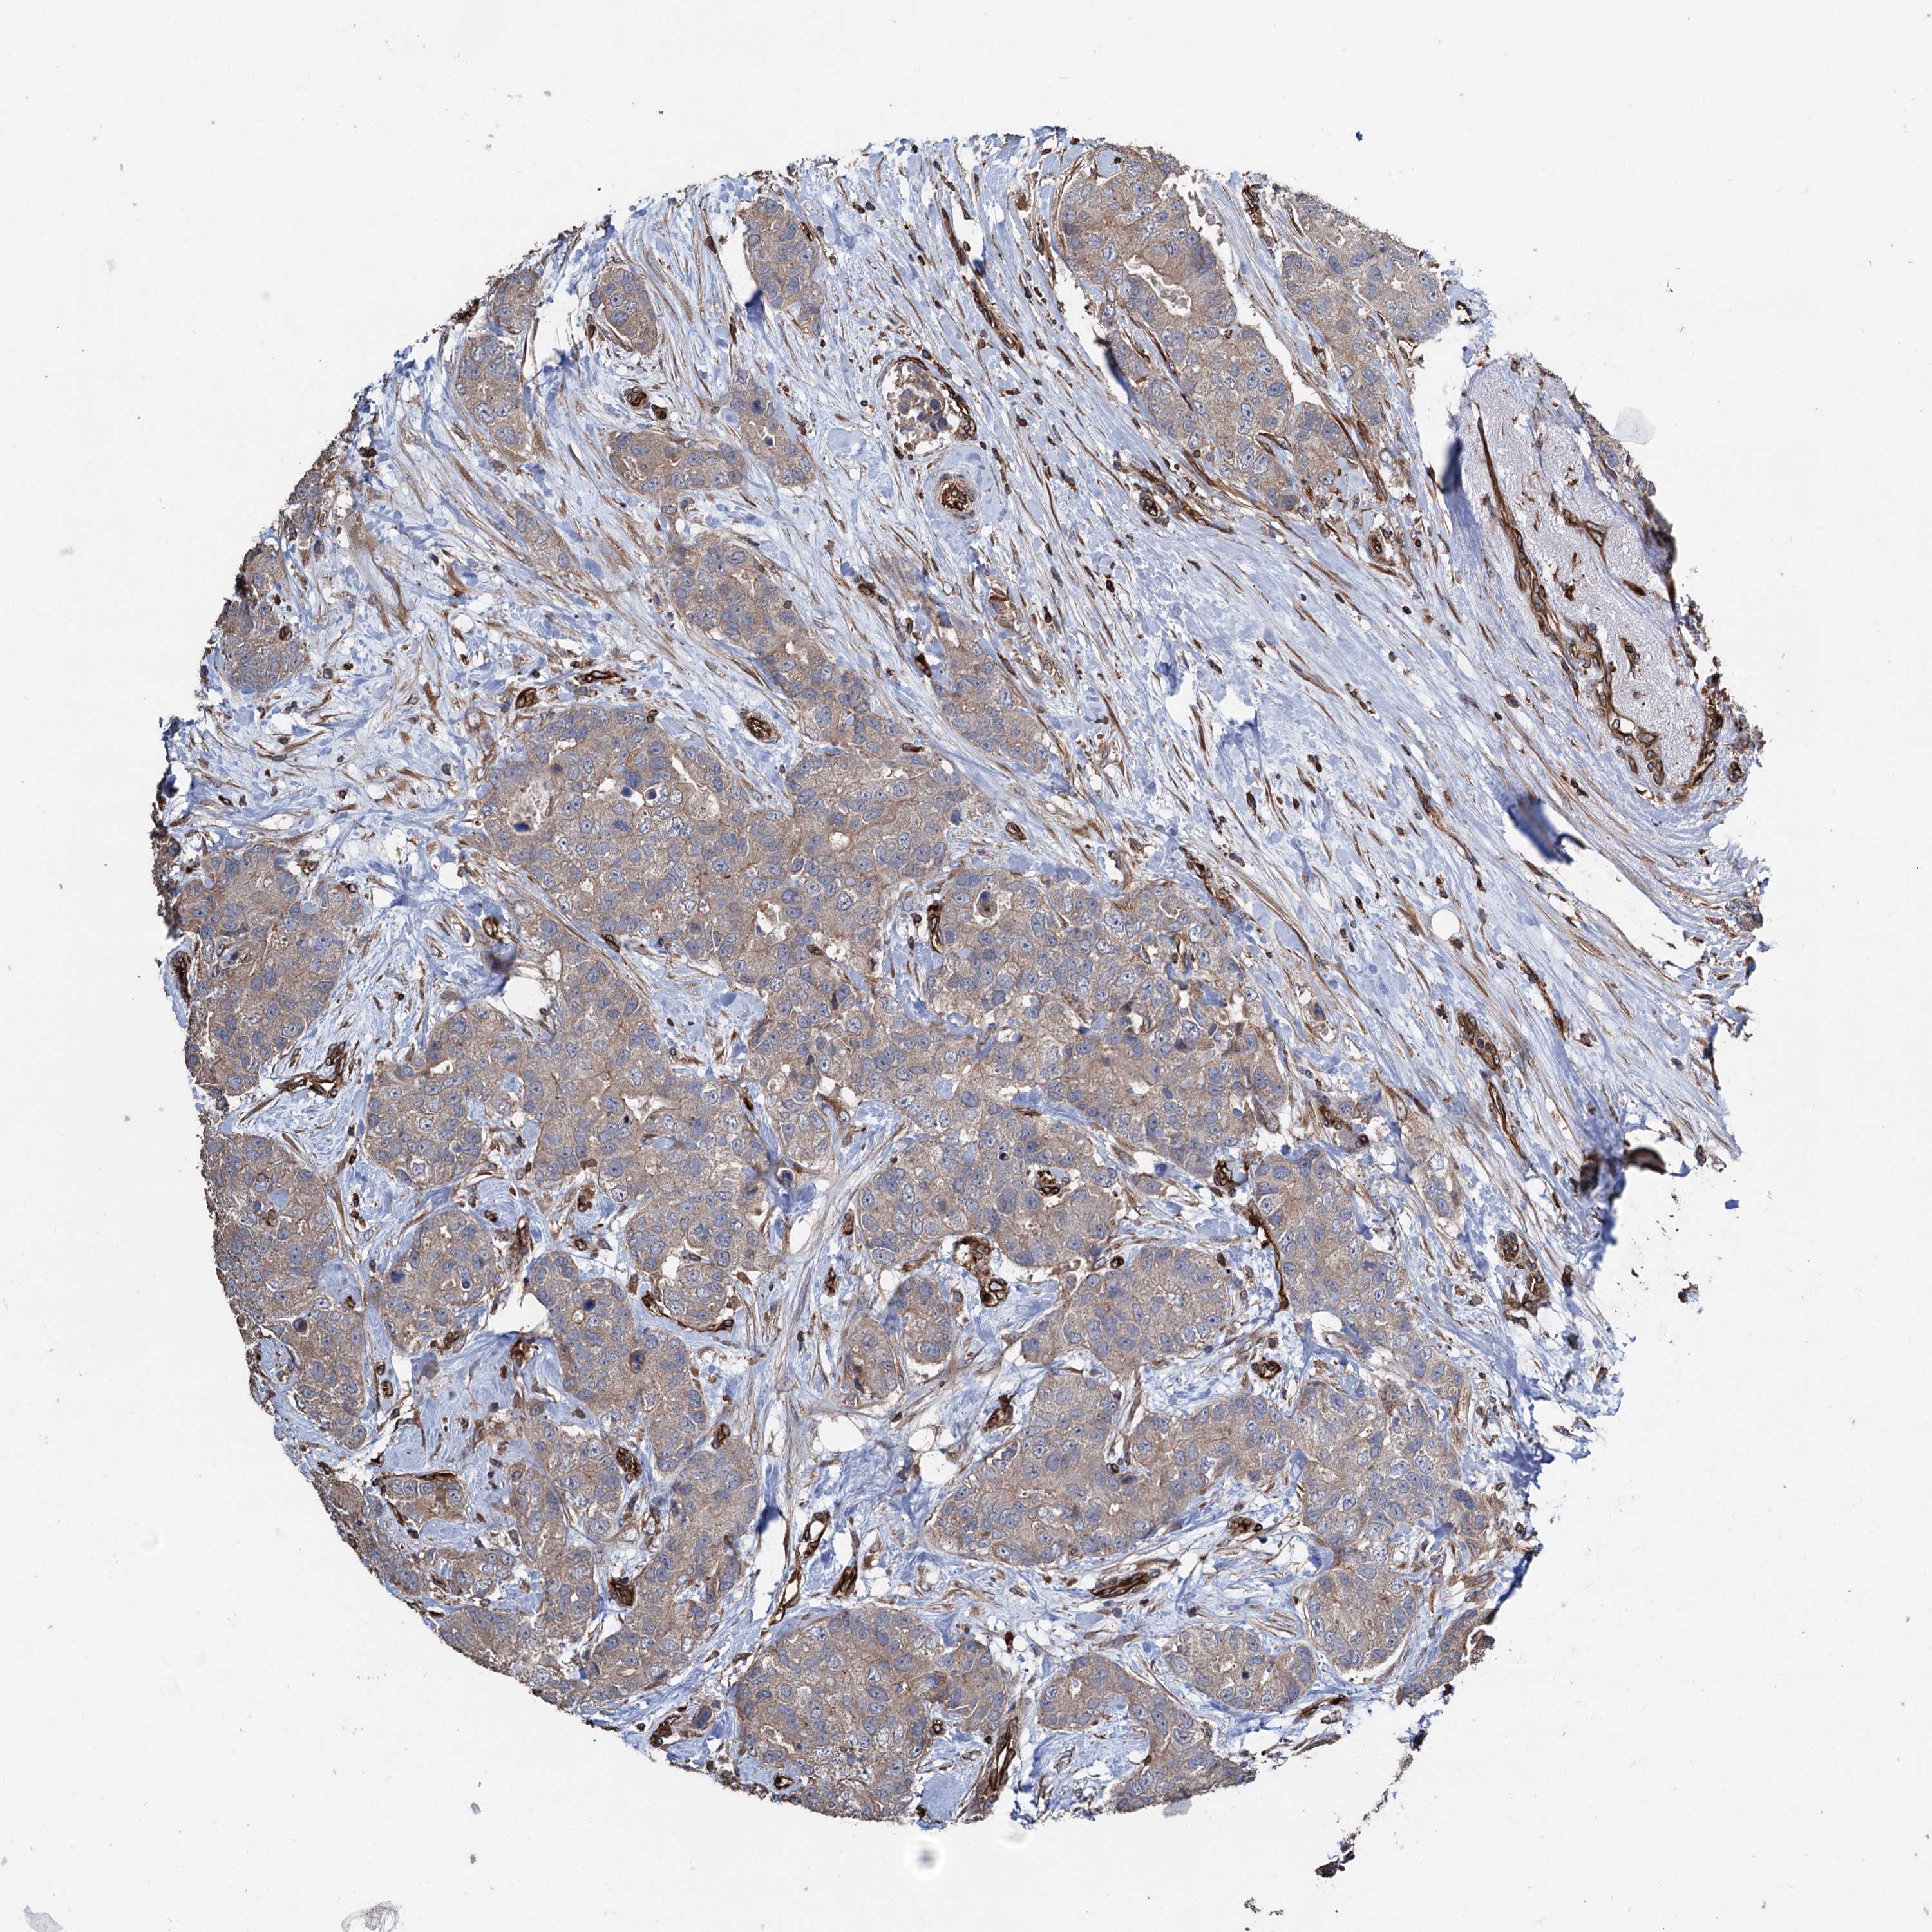

CANCER BREAST CANCER Show tissue menu

BRCA TCGA BRCA VALIDATION PROTEIN EXPRESSION